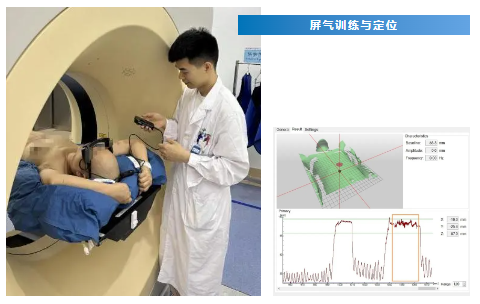

约70%肺癌、乳腺癌等肿瘤患者需要接受放射治疗,但胸部放疗同时会损伤心、肺等重要器官,降低心肺等器官的照射量是改善胸部放疗患者生活质量的关键。为此,放疗机房江丹贤主任,袁戈、吴成省、黄光森等科室骨干在广东医科大学附属医院一专科“一年一突破”战略的指引下,针对呼吸运动引起的内脏运动会导致正常组织照射增加的情况,于2024年6月17日成功开展基于光学体表监测的深吸气屏气放疗技术(DIBH)。

该例患者为乳腺癌保乳术后放疗,经应用深吸气屏气放疗技术后,深吸气使心脏与照射区域的距离拉开,且全肺体积比自然呼吸增加了29%,在保证靶区剂量充足的前提下显著降低了心脏及患侧肺的平均受照剂量,实现乳腺癌患者放疗的高效低毒。